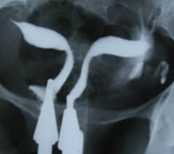

Bicornuate uterus

Atresia of the cervix